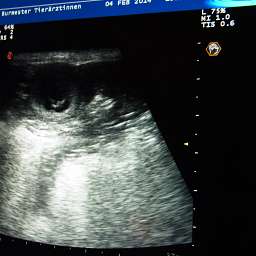

2 Fruchthüllen sind zu sehen

1 Fruchthülle ist zu sehen

Die Fotos sind übrigens durch Anklicken vergrößerbar. Ein Filmchen vom Ultraschall folgt noch. Im Moment fehlt nur die passende Technik zum Hochladen.